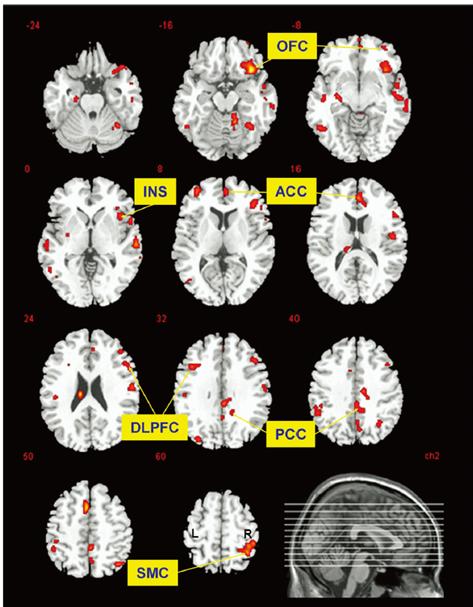

2008 年,Cerebral Cortex 上发布了一篇研究,「看」见了跑步者大脑里的改变[1]。

研究人员招募了 10 名成年男性运动员,让他们跑个半马的距离,即 21 公里左右,再用一种特殊的技术扫描运动员的大脑。

结果发现,与休息状态相比,跑步 30 分钟后,跑步者大脑中阿片类物质和它们受体的结合更加活跃了!

图片来源:参考文献 1阿片类药物系统有多厉害就不用我介绍了吧。